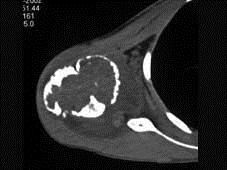

问题 男,29岁,右肩肿物4年,质地硬,压痛不明显,请结合图像,选择最佳答案 ( )

选项 A、巨细胞瘤 B、软骨肉瘤 C、骨转移瘤 D、成软骨细胞瘤 E、结核

答案 D